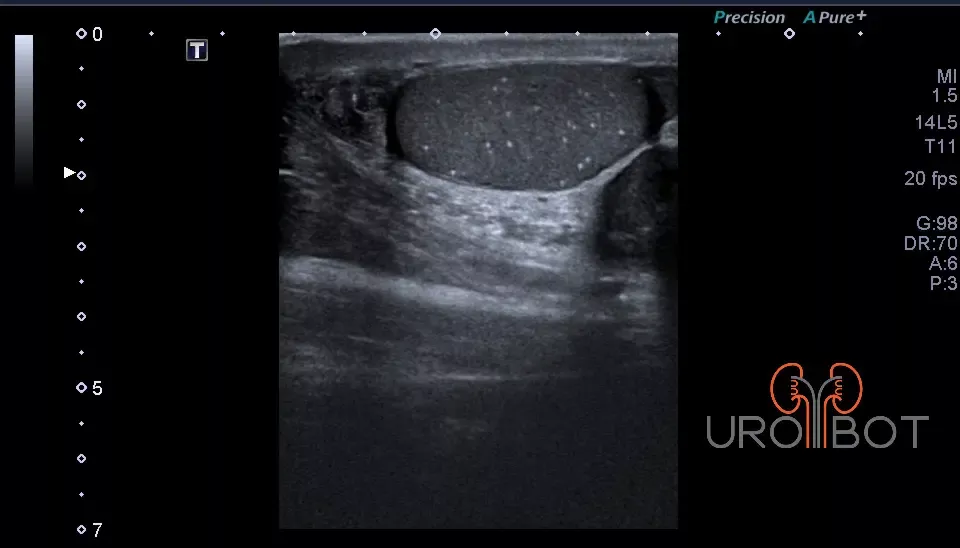

Sonographie des äußeren Genitales

Mit einer stabförmigen Sonde kann die Prostata in zwei oder sogar drei Ebenen sehr gut dargestellt werden.

Es handelt sich bei dieser Untersuchung um eine Ultraschalluntersuchung der Prostata. Dafür wird ein stabförmiger Ultraschallkopf in den Enddarm des Patienten eingeführt. Die Untersuchung kann in Seitenlage oder in Steinschnittlage durchgeführt werden. Mit der speziellen Ultraschallsonde kann die Prostata gleichzeitig längst und quer dargestellt werden. Beurteilt werden:

Prostata: Normalbefund

Auf diesem Bild erkennt man die Prostata in zwei Ebenen mit Hilfe einer in den Enddarm eingeführten Ultraschallsonde.